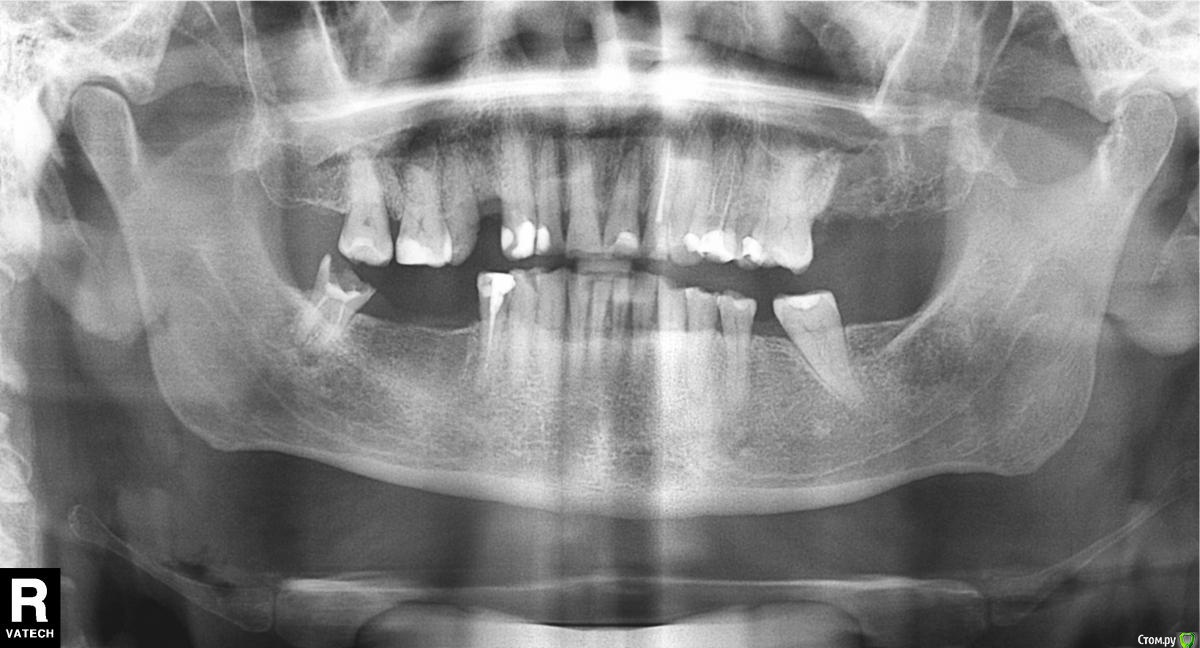

Андрей_П Опубликовано 20 февраля, 2018 Поделиться Опубликовано 20 февраля, 2018 (изменено) Здравствуйте.Прошу помочь разобраться с тонкостями восстановления работоспособности моих зубов.Предполагаю делать имплантацию зубов, панорамный снимок челюстей от 18.02.2018 г. есть.Я – 44 года, живу в Люберцах, мужчина. 13 лет назад была травма челюстей, шинирование на 3 недели, много зубов запломбировали/удалили. Сейчас есть изменения прикуса (предполагаю, из-за отсутствующих длительное время зубов), бруксизма нет, нижние фронтальные 2 зуба истирание о верхние. Курю 30 лет, сейчас 20-30 сигарет в день, повышенный сахар в крови: 5,9-6,8, пью статины.Верхняя 7-ка слева удалена 14.02.2018 г., верхняя 4-ка верхняя удалена июнь 2017 г. Остальные отсутствующие зубы не помню даты удаления, но не менее 6 лет назад.Залечил все пригодные к этому зубы полгода назад. Сейчас, в феврале 2018 г., стоматолог при очном осмотре сказал, что везде костной ткани хватает для классической имплантации (панорамного снимка не видел).Есть желание оставить/восстановить нижнюю 8-ку справа (вкладка, например), но там отсутствие коронковой части, слетела пломба 2 недели назад, стоявшая лет 10, вроде бы около корня киста по снимкам. Есть здоровый антагонист. Нужно ли это?По моим прикидкам (я здесь не специалист совсем) нужно 4-5 имплантов, включая мост (нужен ли мост?) на нижней челюсти справа 2 импланта на 3 отсутствующих зуба. Думаю над Alpha Bio, Osstem, MIS. Нобель не потяну. Хороших врачей на эту задачу не знаю, не сталкивался с этим ранее.Вопросы:1. Сколько может стоить такая имплантация в Москве? Многие клиники заявляют стоимость под ключ имплантация+металлокерамика Альфа Био или Осстем 35-45 тыс. руб. – это реальная цена?2. Можно ли и нужно ли сохранять нижнюю 8-ку и верхнюю 7-ку над ней?3. Нужно ли ставить коронки на фронтальные зубы из-за их истираемости в условиях имплантации отсутствующих зубов? Истираемость возникла именно вследствие отсутствия зубов (до этого её не было), а если поставить импланты на их место, то и стираться нечему будет, такого плотного контакта между передними антагонистами уже не будет, прикус изменится/подкорректируется. Да, нижний передний фронт 2 зуба подстёрлись, верхние антагонисты из-за этого стирания запломбированы полгода назад, но они не болят и не шатаются сейчас.4. Подойдет ли для этой задачи Alpha Bio, Osstem, MIS, что из них лучше? Я так понимаю, нужно с гидрофильной поверхностью типа B+ Альфы, Osstem SLA (SA).5. Нужно ли сразу идти в базальную имплантацию типа ROOT?6. Достаточно ли костной ткани для классической имплантации, если это можно оценить по снимку?7. Как восполнить отсутствующую 6-ку снизу слева и необходимо ли это? 5 и 7 за время отсутствия 6 сместились друг к другу, места под стандартную коронку нет. Мини-имплант или что?8. Нужны ли какие-либо ортодонтические манипуляции (при условии имплантации), если да, то какие и сколько это может занять времени? Буду очень признателен за ответы. Изменено 21 февраля, 2018 пользователем Андрей_П Ссылка на комментарий

Борис80 Опубликовано 21 февраля, 2018 Поделиться Опубликовано 21 февраля, 2018 для полноценной консультации такого снимка недостаточно, мой ответ ни в коем случае не стоит рассматривать как план действий, исходных данных катастрофически мало, это лишь некое направление для ваших мыслей 1. некорректный вопрос, Вы покупаете услугу, а не сам имплант2.недостаточно данных, сложно сказать однозначно,( но чаще такие случаи приводят к удалению 8 зуба - это предположение, недостаточно данных)3.недостаточно данных. Есть только косметические дефекты или снижение прикуса? необходим очный осмотр4. Вы ищите врача, а не поверхность импланта, но мыслите в наиболее благополучном направлении5. ни в коем случае6.недостаточно данных7. ортодонтически поставить зуб 37 в "правильное" положение с помощью мини-импланта - лучшее решение для подобных ситуаций, но конкретно для вашего случая недостаточно данных8. недостаточно данных. ваши вредные привычки и сопутствующие диагнозы не являются абсолютными противопоказаниями для имплантации. Ссылка на комментарий

колесников Опубликовано 21 февраля, 2018 Поделиться Опубликовано 21 февраля, 2018 Здравствуйте! Всего 5 имплантов. Рекомендую Осстем. 8ку справа чтобы сохранить и воостановить,необходимо предварительно пролечить,лечение без гарантии. Приемлемо ли это для Вас решайте сами. 7ку слева необходимо предварительно дистализироовать ортодонтически (в среднем 6 мес). Необходим 3д снимок. Размер 12х8.5(обе челюсти с захватом пазух). Ссылка на комментарий

Андрей_П Опубликовано 22 февраля, 2018 Автор Поделиться Опубликовано 22 февраля, 2018 Спасибо всем врачам за ответы.Постараюсь в ближайшие дни сделать диагностические модели челюстей и КТ 2-х челюстей (это называется 3D, как мне представляется), выложить здесь и спросить опять вас.Колхозить нет желания, я просто спрашиваю, я ни разу не специалист в стоматологии. Боюсь боли и стоматологов с пионерского детства.Был сегодня на очной консультации у ортопеда. Говорит, костной ткани для имплантации отсутствующий зубов более чем достаточно везде. Нижнюю правую 8-ку удалять без вариантов (согласен с этим), на её место ничего не ставить. Сказал, одновременно удалим эту 8-ку и поставим 2 импланта на 6,7 рядом. Меня как чайника это напрягло - будет же свежая лунка на месте 8, потенциальный источник инфекции/проблем для только что зашитых имплантов. Верхнюю 4-ку справа имплантировать не хочет, сказал поставим мост на 3 и 5. Все стоматологи при очном осмотре не находят проблем с дёснами нигде. Да, я покупаю услугу. Но это не значит, что цена на неё не поддаётся исчислению - от 1 рубля до бесконечности.8-ку удалю.Есть изменения прикуса и не начальные. Фронт низ и верх 2-3 зуба стёрлись довольно сильно, они зудят ежедневно, при каждом пережёвывании языком ощущаю, что нижние эти нагреваются, проходит через 1 минуту.Да я и ищу врача, но не нахожу одной клиники, где можно всё это сделать по разумным ценам (да, разумность - понятие очень относительное)."7. ортодонтически поставить зуб 37 в "правильное" положение с помощью мини-импланта - лучшее решение для подобных ситуаций, но конкретно для вашего случая недостаточно данных" - я психологически готов к мимн-импланту, каких данных не хватает?"8. Нужны ли какие-либо ортодонтические манипуляции (при условии имплантации), если да, то какие и сколько это может занять времени?" - в чём недостаточность данных, какая информация нужна? Ссылка на комментарий